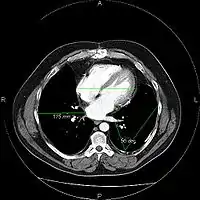

A picture archiving and communication system (PACS) is a medical imaging technology which provides economical storage and convenient access to images from multiple modalities (source machine types).[1] Electronic images and reports are transmitted digitally via PACS; this eliminates the need to manually file, retrieve, or transport film jackets, the folders used to store and protect X-ray film. The universal format for PACS image storage and transfer is DICOM (Digital Imaging and Communications in Medicine). Non-image data, such as scanned documents, may be incorporated using consumer industry standard formats like PDF (Portable Document Format), once encapsulated in DICOM. A PACS consists of four major components: The imaging modalities such as X-ray plain film (PF), computed tomography (CT) and magnetic resonance imaging (MRI), a secured network for the transmission of patient information, workstations for interpreting and reviewing images, and archives for the storage and retrieval of images and reports. Combined with available and emerging web technology, PACS has the ability to deliver timely and efficient access to images, interpretations, and related data. PACS reduces the physical and time barriers associated with traditional film-based image retrieval, distribution, and display.

Most PACS handle images from various medical imaging instruments, including ultrasound (US), magnetic resonance (MR), Nuclear Medicine imaging, positron emission tomography (PET), computed tomography (CT), endoscopy (ES), mammograms (MG), digital radiography (DR), phosphor plate radiography, Histopathology, ophthalmology, etc. Additional types of image formats are always being added. Clinical areas beyond radiology; cardiology, oncology, gastroenterology, and even the laboratory are creating medical images that can be incorporated into PACS. (see DICOM Application areas).